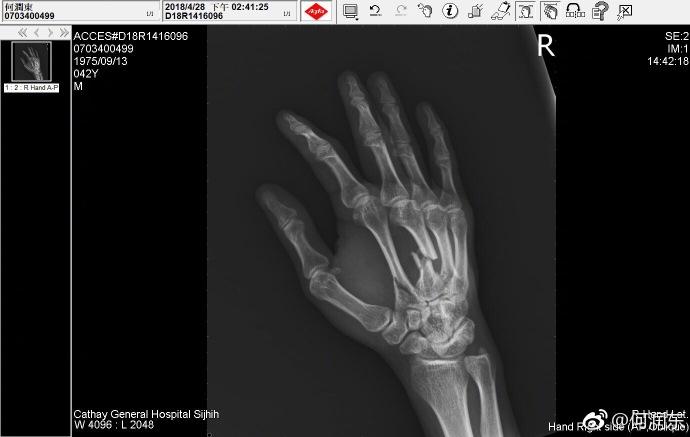

他晒了两张手掌的X光片,确实伤得还蛮重,手背上一根骨头完全骨折,痕迹相当清晰,只是看看也能硬生生地感到疼啊。

不知道他是在拍戏中受的伤,还是健身中。细看X光拍摄的时间,何润东这次受伤是在4月28日。五一劳动节的时候他还用裹着绷带的手给劳动者致敬,裹这么厚,当时就应该想到他伤得重才是。